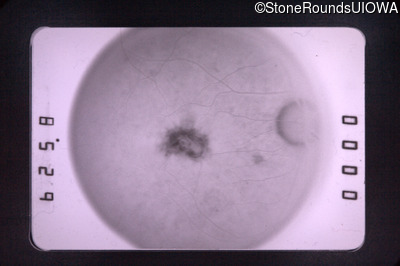

Fundus Photography - Right - 20/70

Exemplar